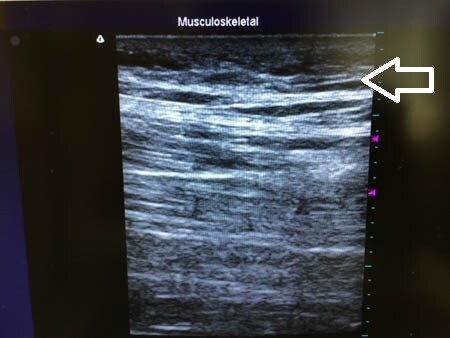

白い矢印部分が皮下脂肪層です。 左太もも正面。